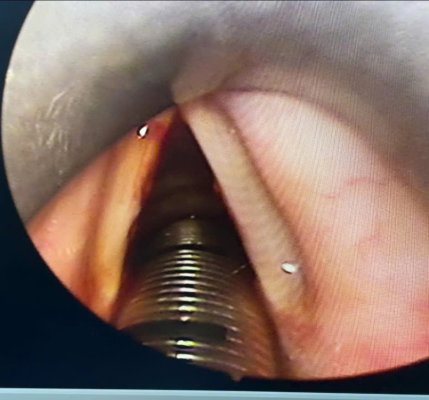

Hình ảnh :U nhú dây thanh (P)

U nhú dây thanh trái trước và sau phẫu thuật của bênh nhân Lê Thị Mỹ T